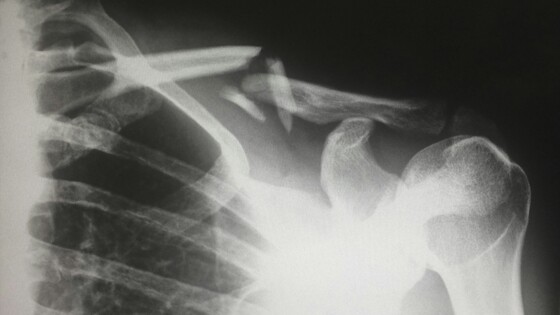

Прыжки на одной ноге могут помочь женщинам старше 55 лет снизить риск переломов и укрепить кости, сказано в исследовании, опубликованном в журнале Journal of Bone and Mineral Research. По словам ученых с факультета спортивной и лечебной физкультуры британского Университета Лафборо, такое высокоинтенсивное упражнение улучшает минеральную плотность кости шейки бедра.

Как сказано в материале, специалисты провели эксперимент с участием 42 женщин в возрасте от 55 до 70 лет, у которых не было противопоказаний к нагрузкам и которые уже как минимум 12 месяцев пребывали в постменопаузе. Отмечается, что в этот период минеральная плотность кости сильно снижается из-за дефицита эстрогена, что приводит к развитию остеопороза.

Когда участниц через шесть месяцев обследовали снова, было установлено, что высокоударные упражнения значительно улучшили минеральную плотность костной ткани шейки бедра женщин. При этом отмечается, что, хотя у пожилых женщин могут быть опасения по поводу того, что прыжки могут навредить суставам, по словам ученых, такие упражнения безопасны.